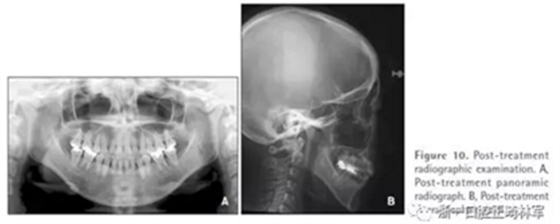

全景片顯示上前牙區(qū)未發(fā)生進(jìn)行性牙根吸收。然而,在下磨牙區(qū)有輕度牙根吸收,并且牙根平行性有改善空間(Figure 10A)。

頭測顯示:下頜平面角從46.7°減小到44.0°。上頜第一磨牙高度減小1.2mm。面高有減小(N-Me: 133.2 mm to 127.7 mm, Ans-Me: 78.5 mm to 72.6 mm; Table 1,Figures 10B and 11)。上下頜切牙顯示腭側(cè)和舌側(cè)傾斜(U1-SN: 95.8°to 91.8°, IMPA: 83.7°to 77.7°)。

治療前后頭影疊加圖清楚地顯示,下頜發(fā)生逆時針旋轉(zhuǎn),上下切牙舌側(cè)移動(Figure 11)。CT顯示髁突未發(fā)生形態(tài)改變,而磁共振T2影像顯示有形態(tài)改善(未提供圖像)。在治療期間沒有出現(xiàn)顳下頜關(guān)節(jié)癥狀。